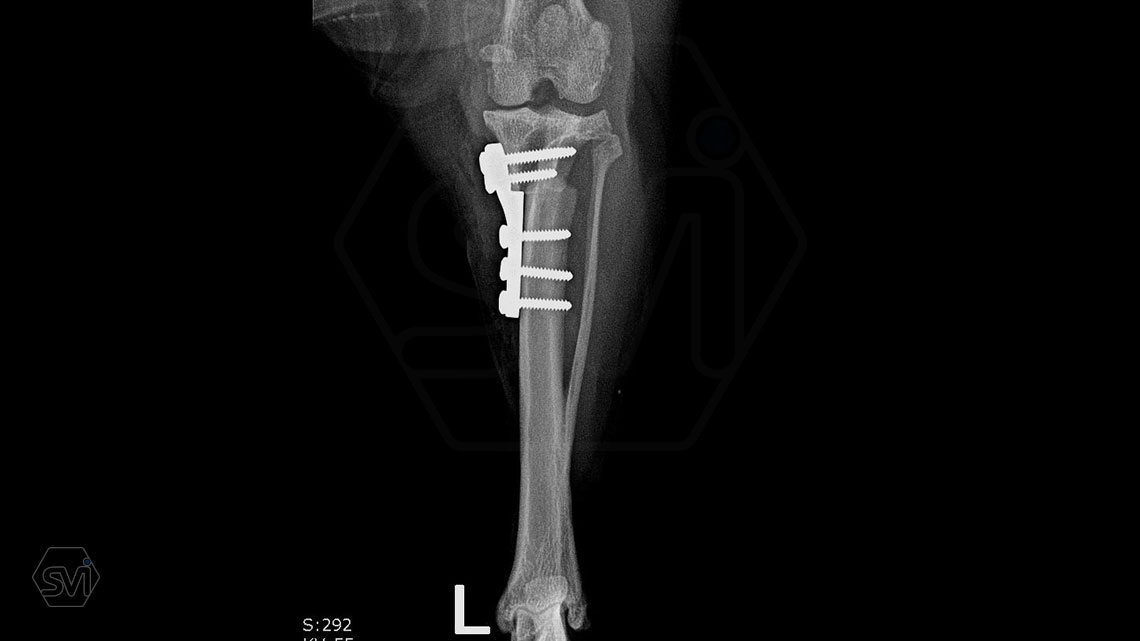

The next step was an osteotomy with a curved saw using an R12 blade and a Smartvet cordless TPLO saw. Since no JIG is used for the operation, the excised bone piece was grasped with a small pointed condylus forceps (small-spitzige) and adjusted to the desired position by the sterile assistant: that an approx. a 2 mm step should be created. This position was fixed with a 1.0 mm K-wire starting from the proximal end of the tuberositas tibiae. The TPLO-M mini plate was used, with a minimal bend, the proximal piece was curved outward for a better fit. The terraced design of the plate was aligned with the 2.2mm step to the bone. Screw insertion order: proximal middle and cranial holes, then distal middle DCP holes (INTRAOP. PICTURE) The three screws were tensioned continuously and alternately, and the temporaly K-wire was removed, thus providing the opportunity for the displacement to be complete and for the osteotomized tibia to assume the position formed by the plate and for compression to develop between bone surfaces. The other screws were then inserted. In our case, the K-wire was no longer returned. (If there is place and way for it, we can put it back a few tenths of a millimeter thicker than the previous one taken out to relieve the crista tibiae. tibiae may break under the load.)

A következő lépés az ívelt fűrésszel való oszteotomia volt, R12 pengét használtunk, és Smartvet akkumlátoros fűrészt. Mivel JIG-et nem használunk a műtéthez, a kivágott csontdarabot kisméretű hegyes condylus-fogóval (kis-spitzige) megragadtuk, és a steril asszisztens a kívánt pozícióba állította: egyrészt a TPA-nak megfelelően elforgatva, majd medialis irányba kiemelve kissé tibia síkjából úgy, hogy egy kb. 2 mm-es lépcső keletkezzen. Ezt a pozíciót egy 1,0 mm -es K szeggel rögzítettük a tuberositas tibiae proximális végétől indítva. A TPLO-M mini lemezt használtuk, egy minimális hajlítással a proximális darabot kifelé görbítettük a jobb illeszkedés végett. A lemez teraszos kialakítását a lépcsőhöz igazítottuk (2,2 mm-es eltolás), és így pozícionáltuk a lemezt. A csavarok behelyezési sorrendje: proximális darab középső és cranialis furat, majd a distalis darab középső DCP furat (INTRAOP. KÉP) A három csavart folyamatosan, felváltva feszítettük, majd a végállapot előtt a pozíciót rögzítő K-szeget a tub. tibiae-ből eltávolítottuk, ezzel biztosítottuk a lehetőségét annak, hogy az eltolás teljes legyen és az oszteotomizált tibia felvegye a lemez által kialakított pozíciót, illetve, hogy kialakuljon a kompresszió csontfelszínek között. A többi csavar behelyezése ezután következett. Esetünkben a K-szeget már nem tettük vissza. (Abban az esetben, ha van hely és mód rá, akkor a kivett előző szegnél néhány tized milliméterrel vastagabbat visszahelyezhetünk a crista tibiae tehermentesítése céljából. Itt ügyelni kell, hogy a szeg soha se menjen a patella egyenes szalagjának tapadási pontja alá, mert a tub. tibiae letörhet a terhelés hatására.)